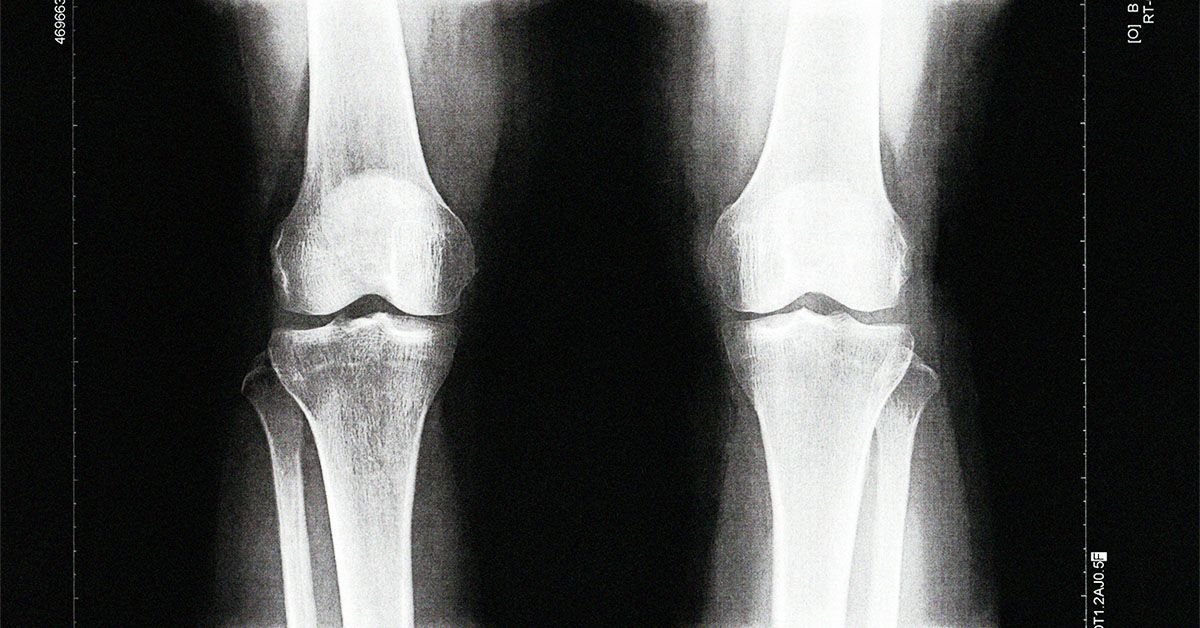

• يعد التهاب المفاصل العظمي حالة شائعة ويتم تشخيصه عادة بالأشعة السينية بعد أن يعاني الشخص من ألم في المفصل.

• أجرى باحثون من جامعة ديوك دراسة حول تشخيص هشاشة العظام في الركبة ووجدوا مؤشرات حيوية في الدم يمكن أن تتنبأ بتطور الحالة.

• وعلم الباحثون أيضًا أن اختبار العلامات الحيوية يمكن أن يتنبأ بالتهاب المفاصل العظمي قبل ما يصل إلى ثماني سنوات من اكتشاف الحالة بواسطة الأشعة السينية.

بحلول الوقت الذي يتم فيه تشخيص إصابة شخص ما بالفصال العظمي عبر الأشعة السينية، يكون يعاني بالفعل من تدهور في غضروفه ومن المحتمل أن يعاني من الألم. إذا كان من الممكن اكتشاف الفصال العظمي قبل حدوث الضرر وظهوره على الأشعة السينية، يعتقد المؤلفون أنه سيكون من الممكن تقديم بعض التدخلات لمنع المرض من التقدم بسرعة.

عند استخدام هذه المؤشرات الحيوية، توقع العلماء بدقة تطور الفصال العظمي في وقت مبكر يصل إلى 8 سنوات قبل ظهور الحالة في التصوير بالأشعة السينية.